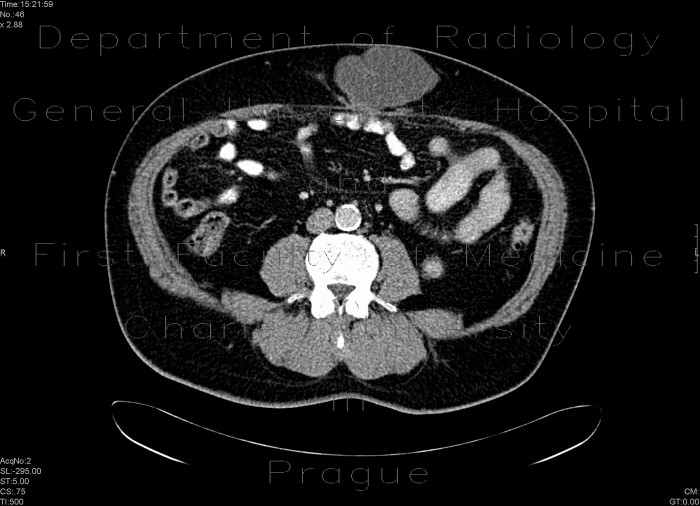

Scar hernia after laparoscopy

Laparscopic insertion of peritoneal catheter complicated by scar hernia which contains omentum and fluid.

Radiology image - Scar hernia after laparoscopy: Abdomen, Peritoneal cavity: CT - Computed tomography